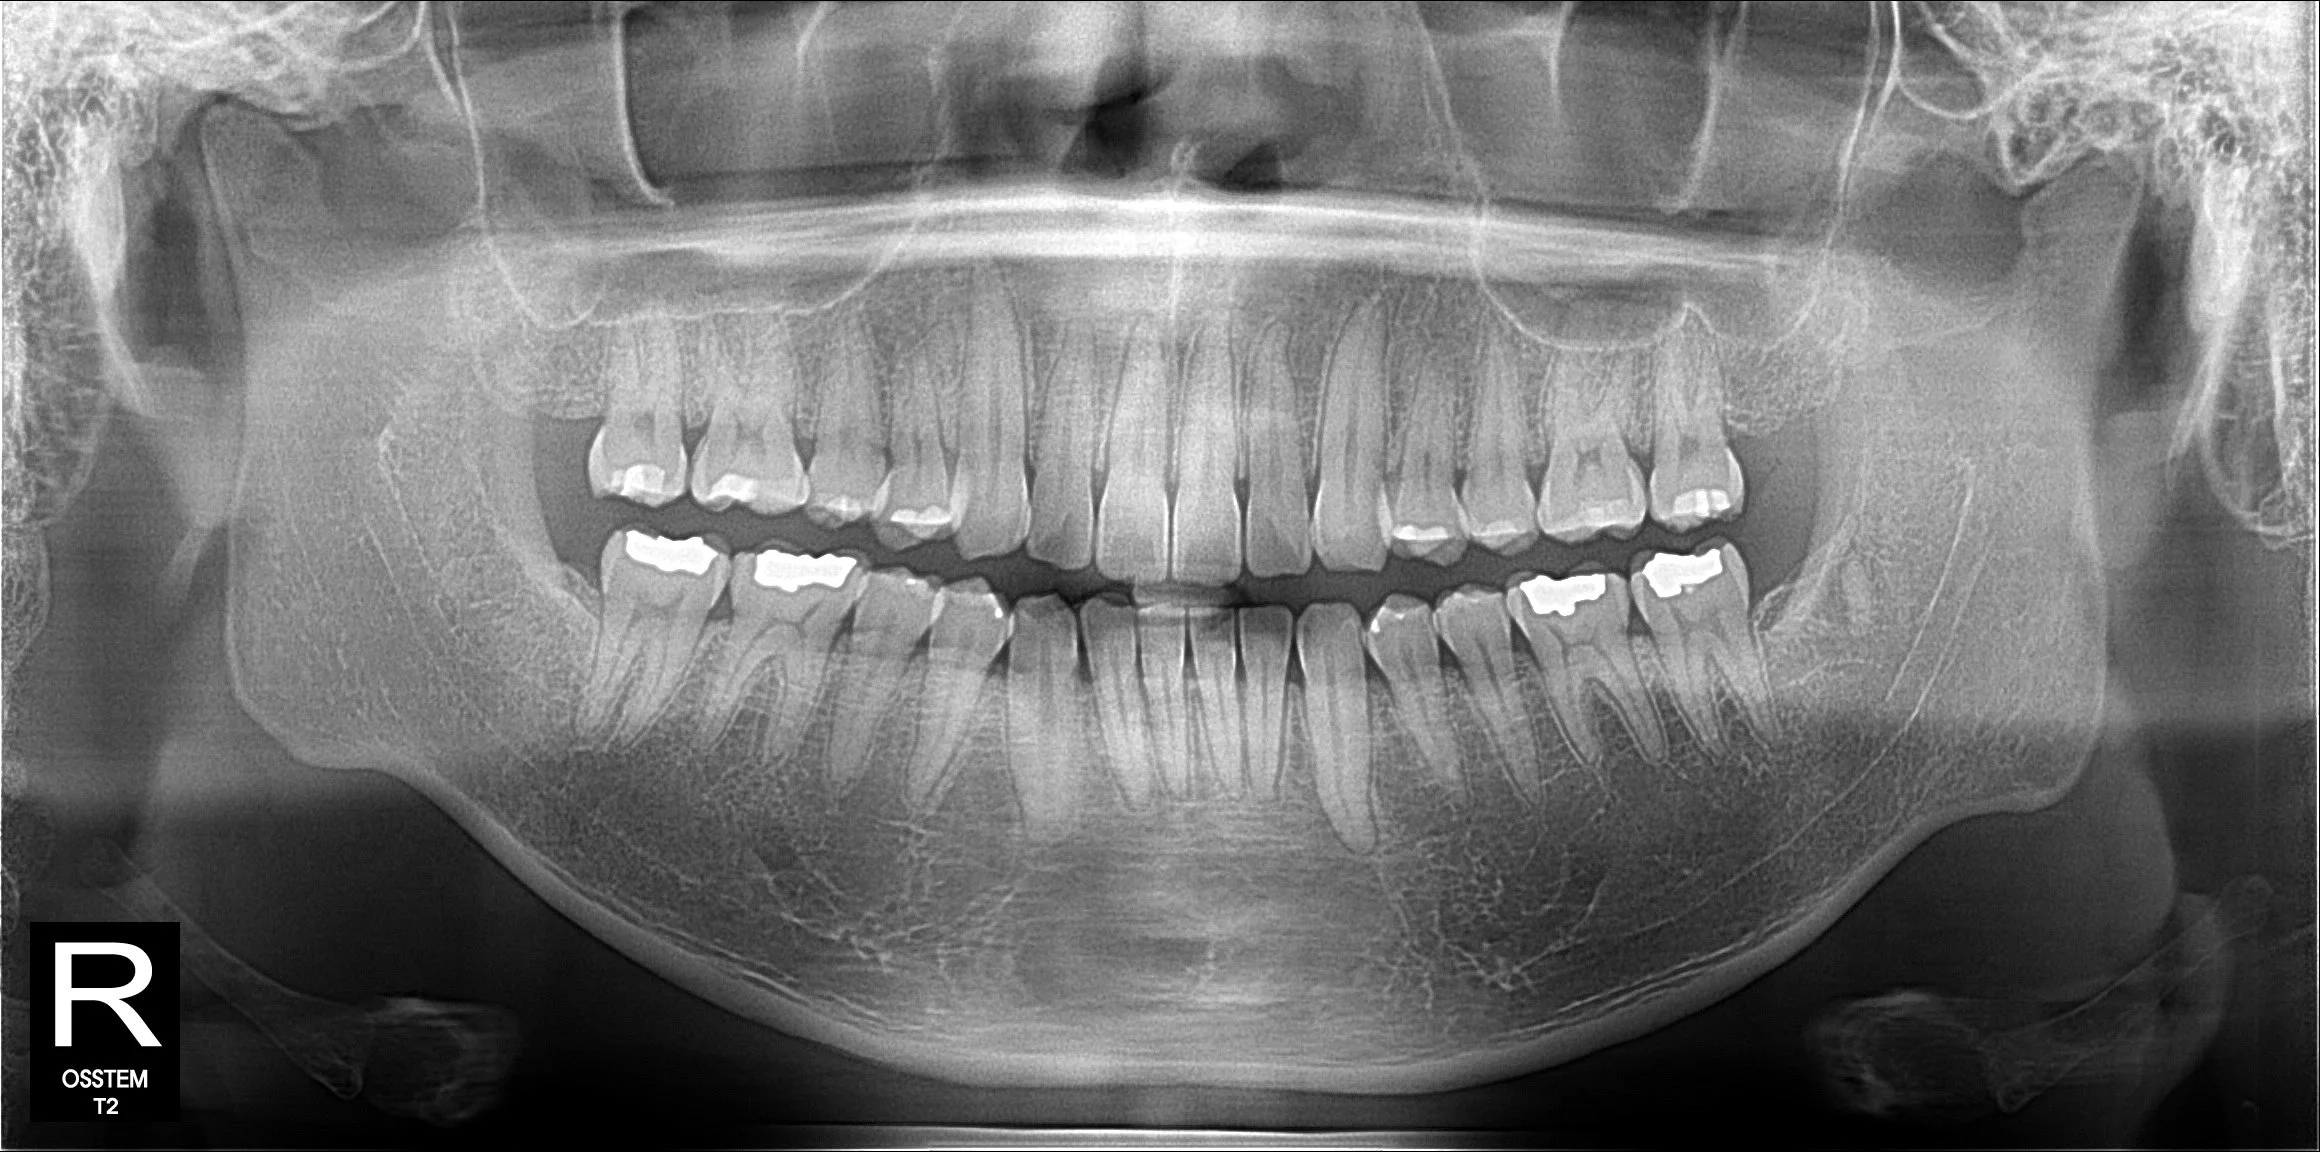

CBCT 연동 시스템: CBCT 데이터를 활용해 잇몸뼈 속 치아 뿌리(치근)의 형태와 위치를 3차원으로 파악합니다. 뿌리의 이동 경로까지 미리 계산하여 더욱 안전하고 정교한 치료 계획을 세웁니다.

눈에 보이는 치아 머리(치관)뿐 아니라 이제 치아 뿌리(치근)까지 확인이 가능하고 시뮬레이션이 가능해졌습니다.